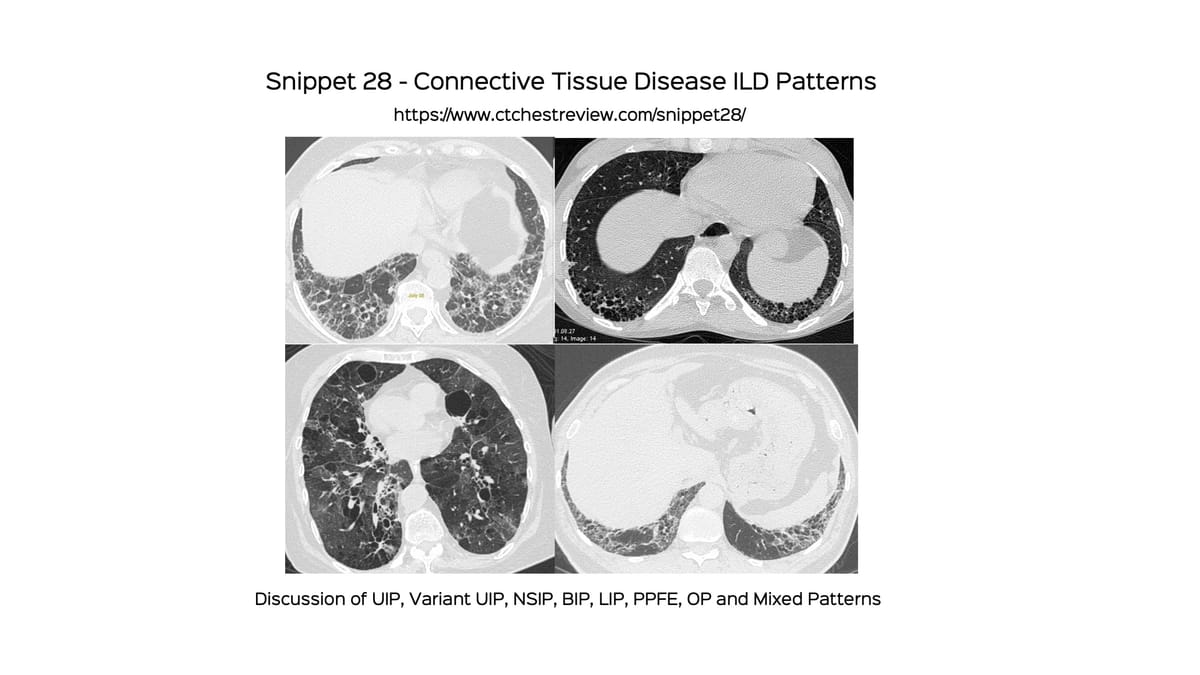

Snippet 29 - IgG4-Related Disease

A discussion of the various manifestations of IgG4-related disease - pulmonary, extrapulmonary and extrathoracic.

IgG4-related disease is an autoimmune process with infiltration of IgG4-plasma cells into tissues. It typically presents as a multi-organ, multicompartmental disease process.

The lung findings are myriad but often non-specific and it is not easy to make a prospective diagnosis, unless there are other organs like the lacrimal glands, salivary glands, pancreas, kidneys, aorta, etc involved.

This video goes through multi-system IgG4-related disease in general and then specifically looks at pulmonary and extra-pulmonary manifestations.